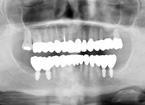

Riabilitazione implanto-protesica completa di paziente disfunzionale, con molteplici fratture ed abrasioni.